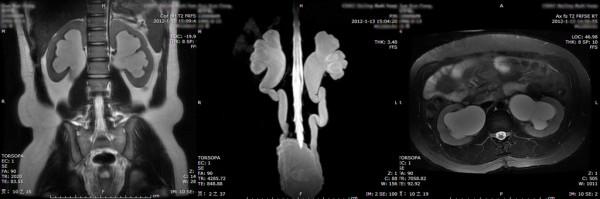

In patients with neurogenic bladder (NB), elevated intravesical pressures can be transmitted to the upper urinary tract, causing hydronephrosis (HN) and ureteral dilation (UD), which are referred to as upper urinary tract dilation (UUTD). Ureteral obstruction at the bladder wall is another cause for UUTD, but is less of a concern. UUTD can lead to chronic renal failure. Therefore, evaluation and protection of UUT function is extremely important in the management for NB. Currently, the most common method by which to detect HN and UD is ultrasonography (US). The Society for Fetal Urology (SFU) established an US HN grading system in 1993, but this system was found to have some defects. The purpose of this study is to describe a new grading system for UUTD, including both HN and UD, based on magnetic resonance urography (MRU) and to correlate the new grading system with the SFU grading system for HN.

A retrospective review of 70 patients with unilateral or bilateral UUTD was completed. Ninety-five sides in patients with UUTD were graded by the MRU-UUTD and SFU-HN grading systems. The results from the two grading systems were compared for each UUTD.

RESULTS

The MRU-UUTD grading system revealed the following percentages for each grade: grade 0, 0; 1, 10.5%; 2, 19%; 3, 42.1%; and 4, 28.4%. The SFU-HN grading system revealed the following percentages for each grade: 0, 0; 1, 10.5%; 2, 19%; 3, 36.8%; and 4, 33.7%. There was no significant systematic difference between the two grading systems (p > 0.05), but a significant difference between grades 3 and 4 (p < 0.05).

在神经源性膀胱(NB)患者中,升高的膀胱内压可向上尿路传递,导致肾盂积水(HN)和输尿管扩张(UD),即上尿路扩张(UUTD)。膀胱壁的输尿管梗阻也是 UUTD 的另一个原因,但不太常见。UUTD 可导致慢性肾衰竭。因此,在 NB 的管理中,评估和保护 UUT 功能至关重要。目前,检测 HN 和 UD 最常用的方法是超声检查(US)。胎儿泌尿外科学会(SFU)于 1993 年建立了超声 HN 分级系统,但该系统存在一些缺陷。本研究旨在描述一种基于磁共振尿路成像(MRU)的新的 UUTD 分级系统,包括 HN 和 UD,并将新分级系统与 SFU 的 HN 分级系统进行相关性分析。

对 70 例单侧或双侧 UUTD 患者进行回顾性分析。95 侧 UUTD 患者的 MRU-UUTD 和 SFU-HN 分级系统进行分级。比较两种分级系统对每侧 UUTD 的分级结果。

结果

MRU-UUTD 分级系统显示每个等级的百分比如下:0 级,0;1 级,10.5%;2 级,19%;3 级,42.1%;4 级,28.4%。SFU-HN 分级系统显示每个等级的百分比如下:0 级,0;1 级,10.5%;2 级,19%;3 级,36.8%;4 级,33.7%。两种分级系统之间没有显著的系统差异(p>0.05),但 3 级和 4 级之间有显著差异(p<0.05)。